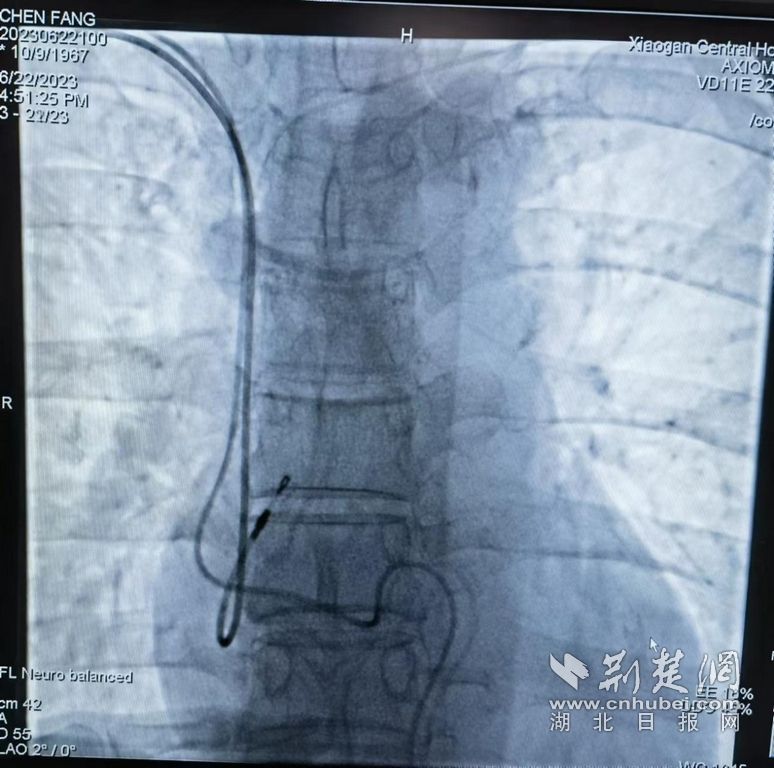

七年前,陈女士因心动过缓,在外省经右侧锁骨下静脉置入永久心脏起搏器。今年6月初,她因乳腺恶性肿瘤被孝感中心医院普外科甲乳病区收治。为保障患者化疗期间用药安全,需建立一条长期的中心静脉通路。

由于患者带有起搏器,此时的中心静脉置管可能存在“双生命线”狭路相逢的困境。静脉治疗组长张小莉启动静脉治疗N-MDT会诊流程,邀请心内科、心外科、介入科、PICC门诊、感染科的专家会诊,确定经患者左侧上臂置入PICC导管的可行性。

6月22日,张小莉陪同患者到介入科完成置管。目前患者在心电监护下,顺利完成第一周期的化疗,期间未出现心前区不适、心动过缓等情况。